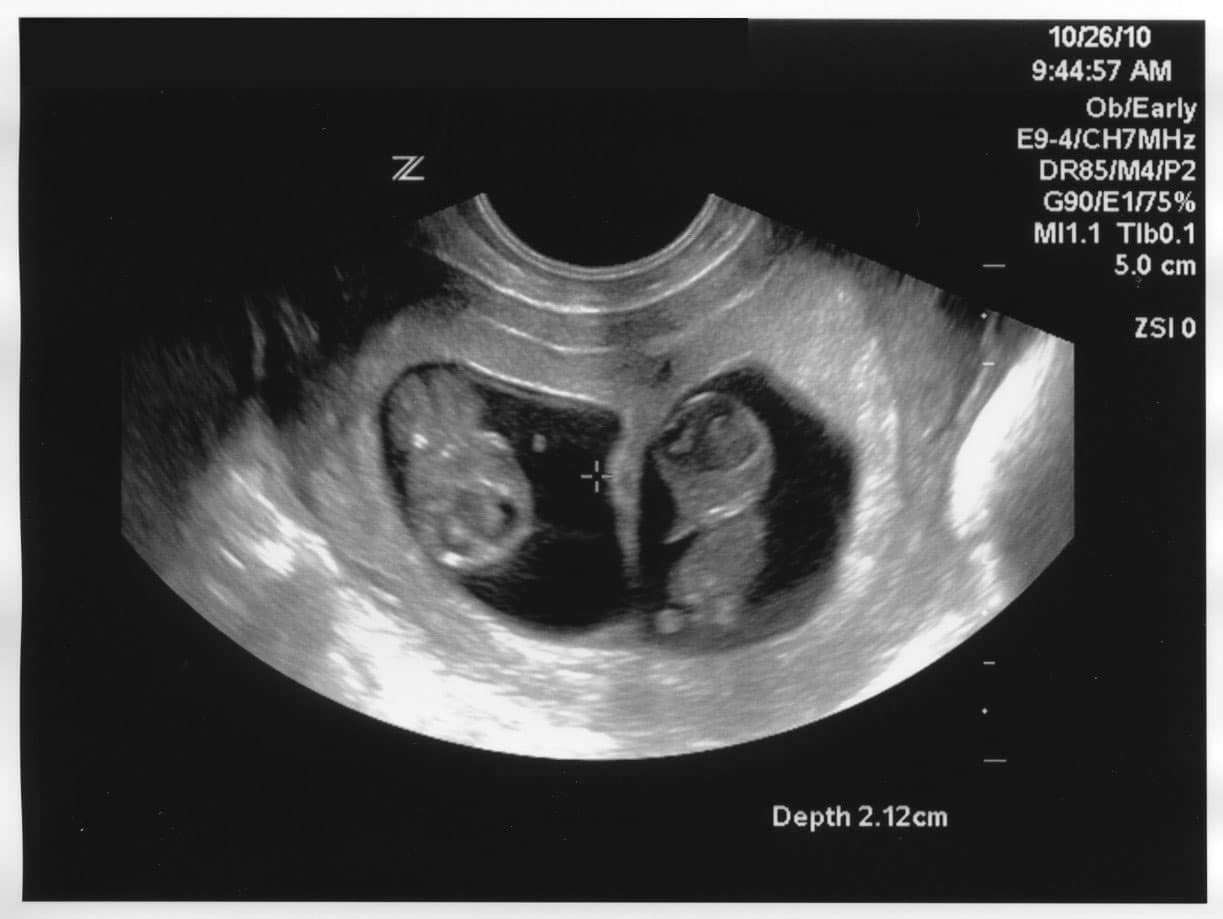

SpsoredMatt ve Jody Parry çifti, tek yumurta ikizleri olacağını duyduğunda sevinçten havalara uçtu. Oğulları da evin büyük ağabeyi olacağı için çok heyecanlıydı! Fakat doğumdan kısa süre sonra doktor Matt ve Jodi’yle özel görüşmek isteyerek Jodi’nin asla unutamayacağı özel bir şey söyledi…